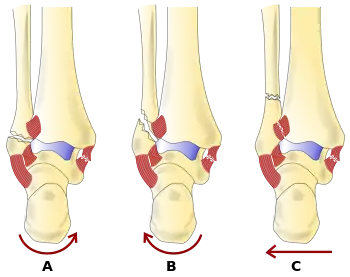

Danis–Weber classification of ankle fractures (Types A, B and C)

The Danis–Weber classification (often known just as the Weber classification) is a method of describing ankle fractures. It has three categories:[1]

Type A

Fracture of the fibula distal to the syndesmosis (the connection between the distal ends of the tibia and fibula). Typical features:

• below level of the ankle joint

• tibiofibular syndesmosis intact

• deltoid ligament intact

• medial malleolus occasionally fractured

• usually stable: occasionally nonetheless requires an open reduction and internal fixation (ORIF) particularly if medial malleolus fractured

Type B

Fracture of the fibula at the level of the syndesmosis. Typical features:

• at the level of the ankle joint, extending superiorly and laterally up the fibula

• tibiofibular syndesmosis intact or only partially torn, but no widening of the distal tibiofibular articulation

• medial malleolus may be fractured or deltoid ligament may be torn

• variable stability

Type C

Fracture of the fibula proximal to the syndesmosis. Typical features:

• above the level of the ankle joint

• tibiofibular syndesmosis disrupted with widening of the distal tibiofibular articulation

• medial malleolus fracture or deltoid ligament injury present

• unstable: requires ORIF

Categories B and C imply a degree of damage to the syndesmosis itself (which cannot be directly visualised on X-ray). They are inherently unstable and are more likely to require operative repair to achieve a good outcome. Type A fractures are usually stable and can be managed with simple measures, such as a plaster of paris cast.